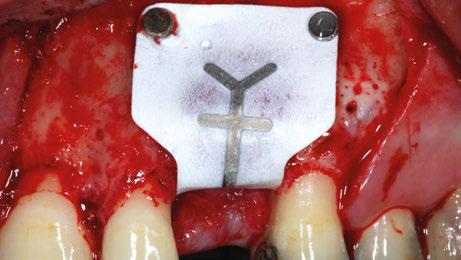

Figura 4. Fijación de la membrana no reabsorbible (Goretex®).